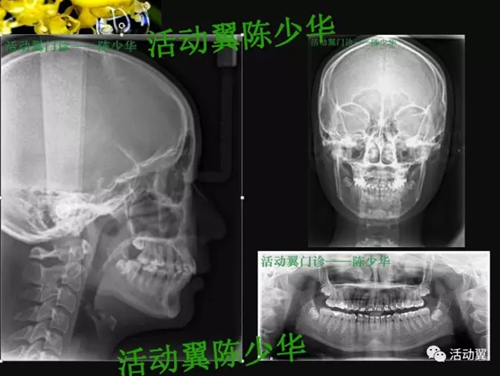

活動翼舌側(cè)病例——安氏2類1分類

•主訴:上牙前突,上下牙不齊,要求矯正。•牙列檢查:年輕恒牙17-27、37-47。磨牙尖牙遠中關(guān)系;前牙覆蓋6MM,深覆合2度,上牙前傾,下前牙輕度擁擠,Spee曲深。•面型:直面型。下頜輕度后縮。上下頜骨突度正常。顳下頜功能檢查未發(fā)現(xiàn)明顯異常。